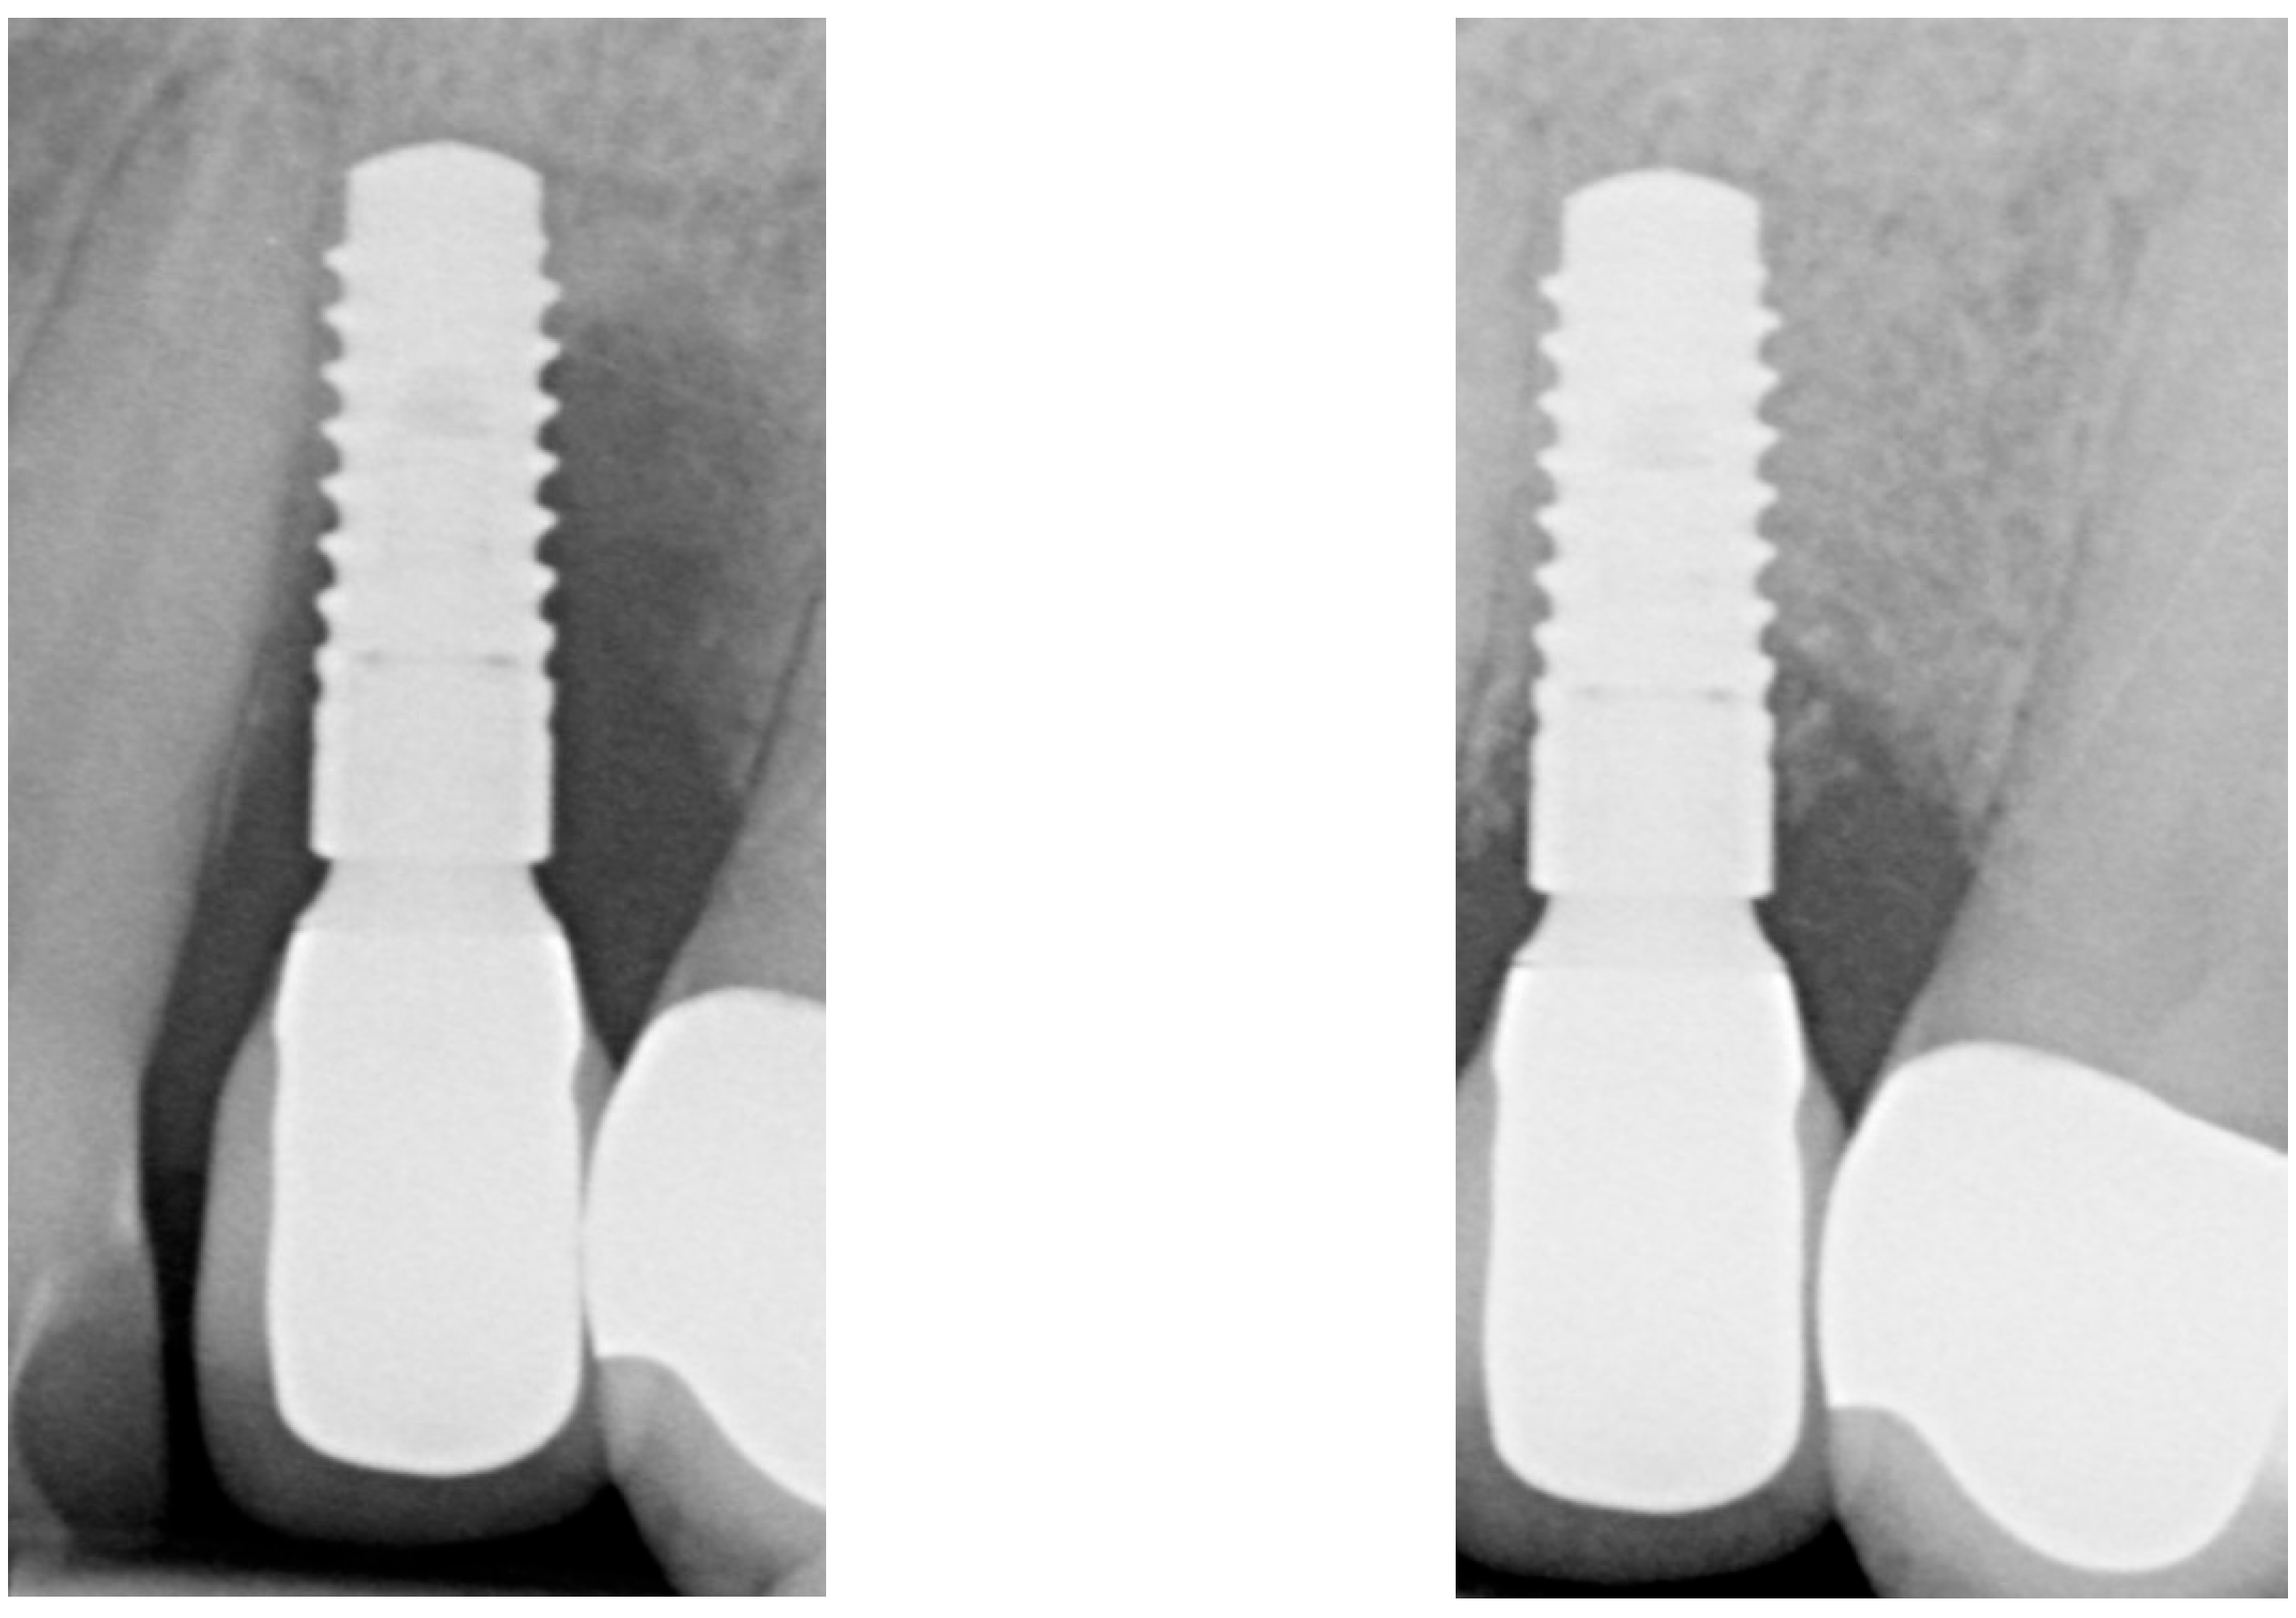

| Radiographic bone level at Tpre mesial (mm) | 5.6 | 3.8 | 1.7 |

| Radiographic bone level at Tpre distal (mm) | 7.6 | 4.2 | 3.2 |

| Radiographic bone level at T2 mesial (mm) | 0.4 | 3.5 | 0.0 |

| Radiographic bone level at T2 distal (mm) | 1.8 | 3.9 | 0.0 |

| Radiographic bone level at T6 mesial (mm) | 2.8 | 3.4 | 1.1 |

| Radiographic bone level at T6 distal (mm) | 3.5 | 0.7 | 2.5 |

| Radiographic bone level at T12 mesial (mm) | 2.3 | 2.5 | 1.7 |

| Radiographic bone level at T12 distal (mm) | 3.5 | 1.5 | 2.5 |